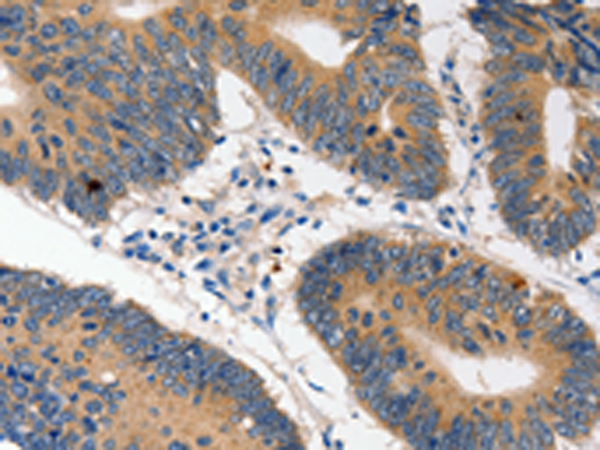

分类: 科研抗体货号: P07391别名: LPS; PIT; PPS; VWS; OFC6; PPS1; VWS1应用: WB,IHC反应种属: Human, Mouse